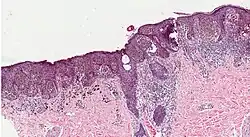

Histopathologic types

Melanoma is a type of neuroectodermal neoplasm.[85] There are four main types of melanoma:[86]

SN Type Features Incidence[86][notes 1] Photograph Micrograph

1. Superficial spreading melanoma Melanoma cells with nest formation along the dermo-epidermal junction. 70%

2. Nodular melanoma Grows relatively more in depth than in width. 15% - 20%

3. Lentigo maligna melanoma Linear spread of atypical epidermal melanocytes as well as invasion into the dermis.[87] 5% - 10%

4. Acral lentiginous melanoma Continuous proliferation of atypical melanocytes at the dermoepidermal junction.[88] 7% - 10%